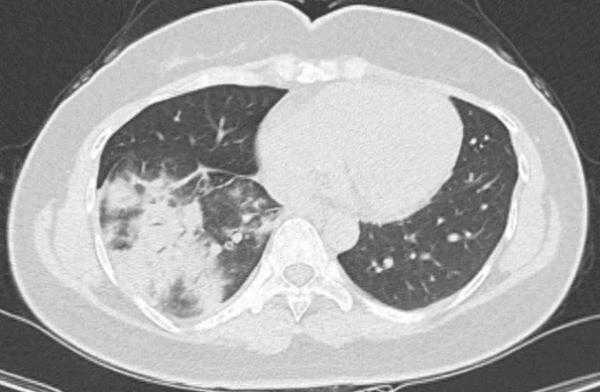

治疗前胸部CT片显示右肺下叶可见多发小片状、斑片状密度增高影

医生通过支气管镜检查,发现朱女士的右下肺支气管有大量黄白色黏痰,通过快速病原学检测发现了“肺炎支原体”。也就是说,朱女士不仅感染了肺炎支原体,病情还比较严重,被确诊为肺炎支原体肺炎。